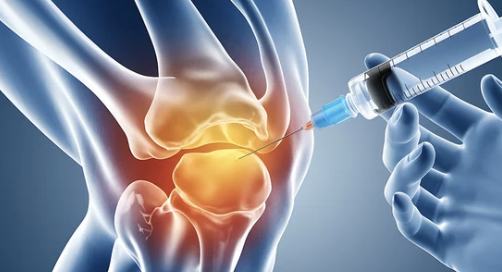

1. 무릎 인공관절 수술, 왜 필요할까? 📌

✔ 퇴행성 관절염이 심해지면 무릎 연골이 닳아 뼈끼리 부딪히며 심한 통증 유발

✔ 일상생활이 어려워지고 걷기조차 힘들어질 수 있음

✔ 수술을 통해 손상된 관절을 인공관절로 대체하면 통증 완화 & 활동 가능